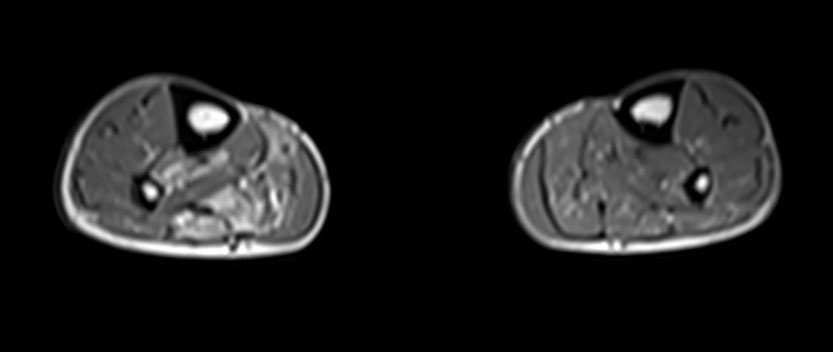

Der geübte Untersucher kann anhand des seitlichen Röntgenbildes die Diagnose einer Achillessehnenruptur stellen. Die Konturen des Kager-Dreiecks – gebildet von der ventralen Begrenzung der Achillessehne, der posterioren Tibiakante und der kranialen Kalkaneuskortikalis – verstreichen im Rupturfall (Kager 1939). Die MRT- Diagnostik spielt für die Primärdiagnostik der frischen Achillessehnenruptur eine untergeordnete Rolle und ist im Normalfall nicht notwendig. Anders verhält es sich bei den chronischen Rupturen. Hier ist die MRT ein wichtiges Diagnostikum insbesondere in Hinblick auf die Beurteilung der Sehnen- und Muskeldegeneration (Abb. 6).

Abbildung 6

Neben der strukturellen Wiederherstellung der Sehne ist die funktionelle Beurteilung des Muskels von entscheidender Bedeutung. Ist es bereits zu einer Degeneration der Muskeln gekommen, kann ein gutes funktionelles Ergebnis, trotz subtiler Sehnenrekonstruktion, nicht erreicht werden. Die Arbeitsgruppe um Hoffmann et al. 13 konnte in ihrer Arbeit zeigen, das es - ähnlich wie bei Patienten mit chronischen Supraspinatusrupturen - zu fettigen Degenerationen und Ödemen der Muskulatur kommt, die im MRT nachweisbar sind. Wir empfehlen die MRT- Untersuchung des gesamten Unterschenkels und nicht nur die rupturnahen Bereiche. Des Weiteren lässt die MRT eine Beurteilung der Degeneration der umliegenden Sehnenanteile zu. Die Computertomographie sollte nur in Ausnahmefällen zum Ausschluss von Begleitverletzungen (Abb. 7) durchgeführt werden und gibt uns sonst keinen weiteren Informationsgewinn.